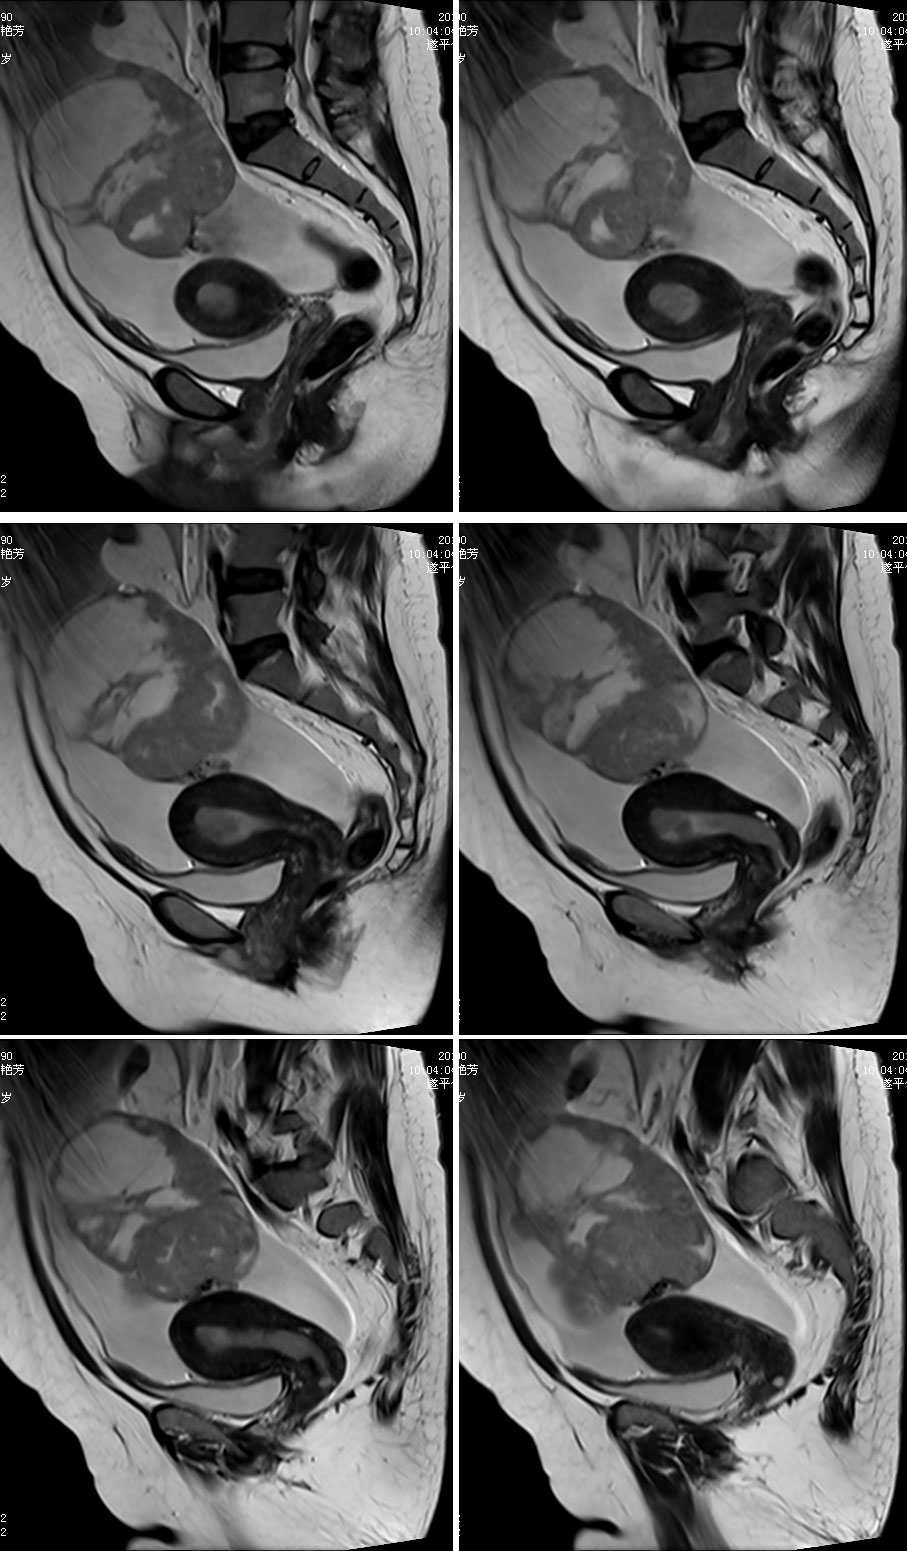

CL2918:卵巢癌

女性,47岁。卵巢癌已确诊

卵巢癌已确诊